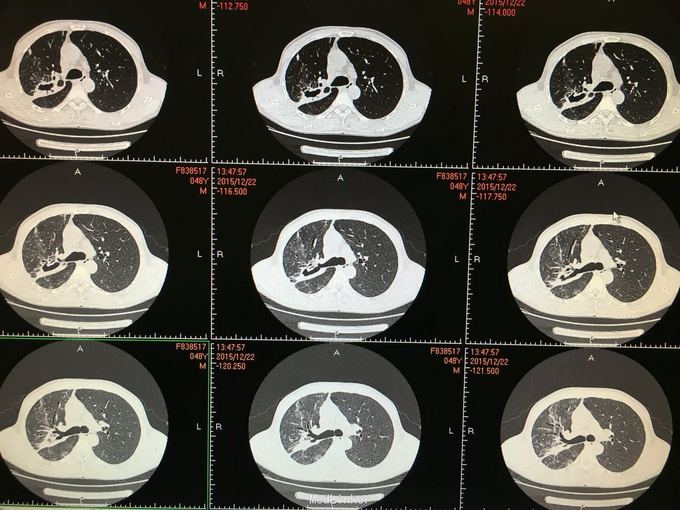

间断咳嗽咳痰5月余。患者缘于半年前确诊为骨髓增生异常综合征,并行造血干细胞移植术。术后出现发热,完善相关检查考虑为肺部真菌感染,给予抗感染治疗后体温正常,病情好转出院。出院后仍有间断咳嗽咳痰,咳黄色痰,无发热,自行口服伏立康唑200mg,2/日治疗,12月初复查CT提示双肺病灶较前进展,右肺中叶新增病灶。

根据症状体征及辅助检查,结合病史考虑真菌感染可能性大。进一步气管镜检查,结果如下。组织活检标本可见。病理回报提示真菌团,培养见曲霉菌生长。明确诊断后给予两性霉素B雾化吸入及伏立康唑静脉应用抗真菌治疗,同时给予环孢素口服。

造血干细胞移植后肺部感染常见,其中以曲霉、卡肺等多见,患者经气管镜检查已将真菌团块取出。术后给予监护,口服云南白药、垂体后叶素雾化止血等治疗,无明显出血,症状逐渐好转。复查CT也明显好转。